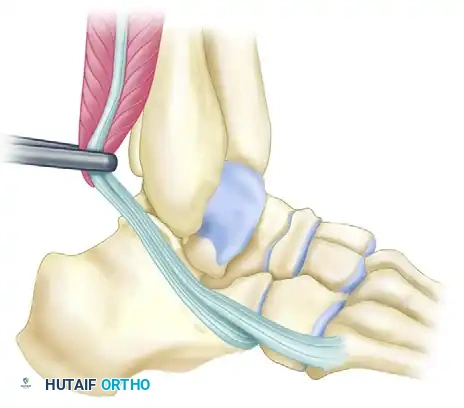

Advanced Surgical Reconstruction: Peroneus Longus Transfer

In cases of profound instability where the talus exhibits significant valgus tilt and standard retinacular repairs are insufficient, a complex rerouting of the peroneus longus can be employed to act as a dynamic and static checkrein.

- Talar Tunnel Creation and Graft Passage:

Identify the peroneus longus tendon and prepare the graft. Drill a tunnel through the body of the talus, directing the guide pin from lateral to medial. Pass the peroneus longus graft through the talar tunnel. Apply strict tension to the graft and secure it at the medial end of the tunnel using an appropriately sized interference screw. - Tibial Tunnel Creation:

Create a second osseous tunnel starting at the tip of the medial malleolus, specifically within the intercollicular groove. Angle this tunnel proximally and laterally at approximately 60 degrees so that it exits in the distal third of the tibia, just anterior to the fibula.

> Surgical Warning: Extreme care must be taken during the trajectory planning and drilling of this tibial tunnel to avoid violating the medial articular surface of the tibial plafond. - Graft Routing and Tensioning:

Retrieve the peroneus longus graft from the medial talus and bring it through the newly created tibial tunnel, passing it from medial to lateral. Apply rigorous graft tensioning while manually reducing the valgus tilt of the talus to restore neutral hindfoot alignment. - Lateral Fixation:

Secure the exiting peroneus longus graft onto the lateral border of the tibia. A combination of a tenodesis screw and a supplemental staple is highly preferred for rigid biomechanical fixation. Alternatively, the graft can be secured directly to the fibula utilizing a screw post or a spiked washer, depending on bone quality and surgeon preference. - Concomitant Deformity Correction: